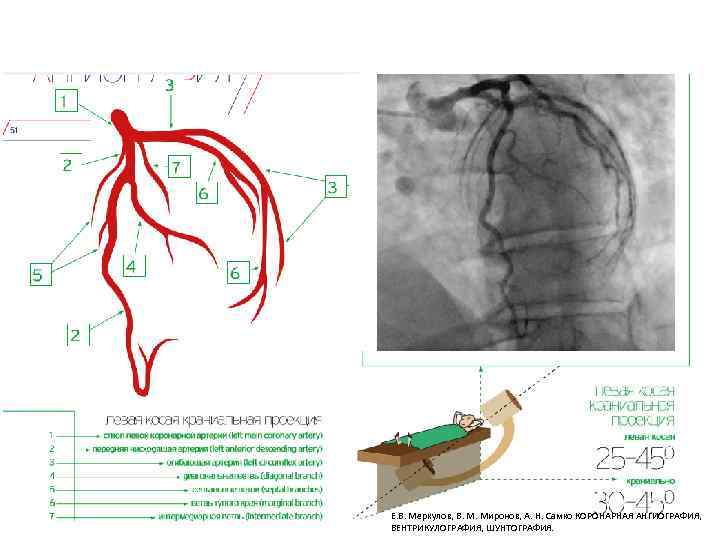

Левая коронарная артерия Е. В. Меркулов, В. М. Миронов, А. Н. Самко КОРОНАРНАЯ АНГИОГРАФИЯ, ВЕНТРИКУЛОГРАФИЯ, ШУНТОГРАФИЯ.

Е. В. Меркулов, В. М. Миронов, А. Н. Самко КОРОНАРНАЯ АНГИОГРАФИЯ, ВЕНТРИКУЛОГРАФИЯ, ШУНТОГРАФИЯ.